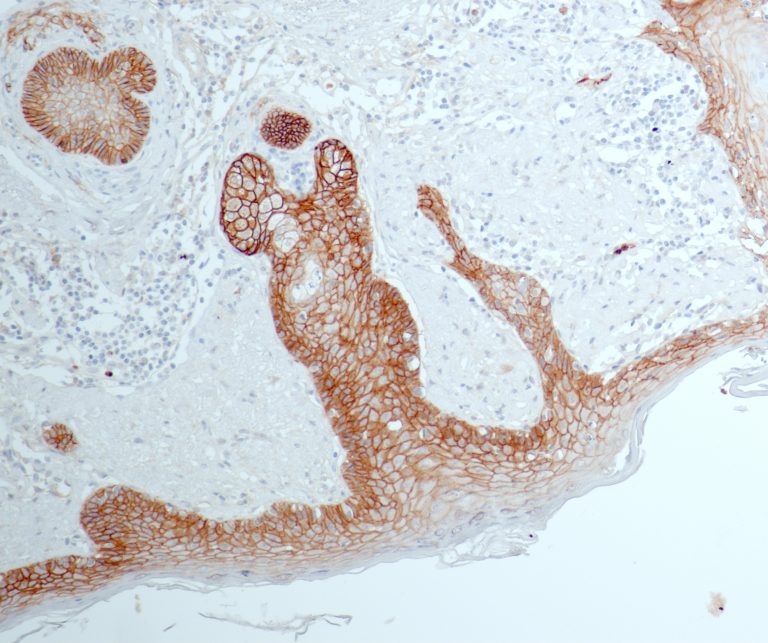

Vascular Pathology

Gastrointestinal (GI) Pathology

General Marker

Breast Pathology

Endocrine Pathology

Gynecological Pathology

Neuropathology

Infection Markers

Lung Pathology

Urinary Tract Pathology

Transplantation Pathology

Soft Tissue Pathology

Hematopathology